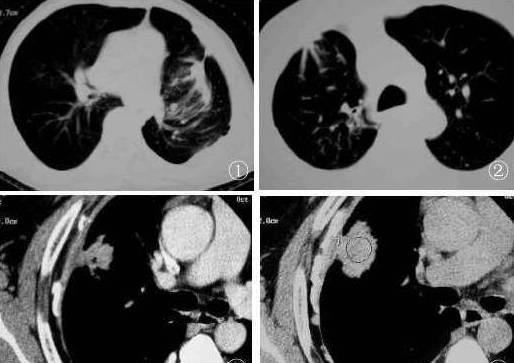

↓ 右肺中央型肺癌(鳞癌)并右下肺不张(X、CT)